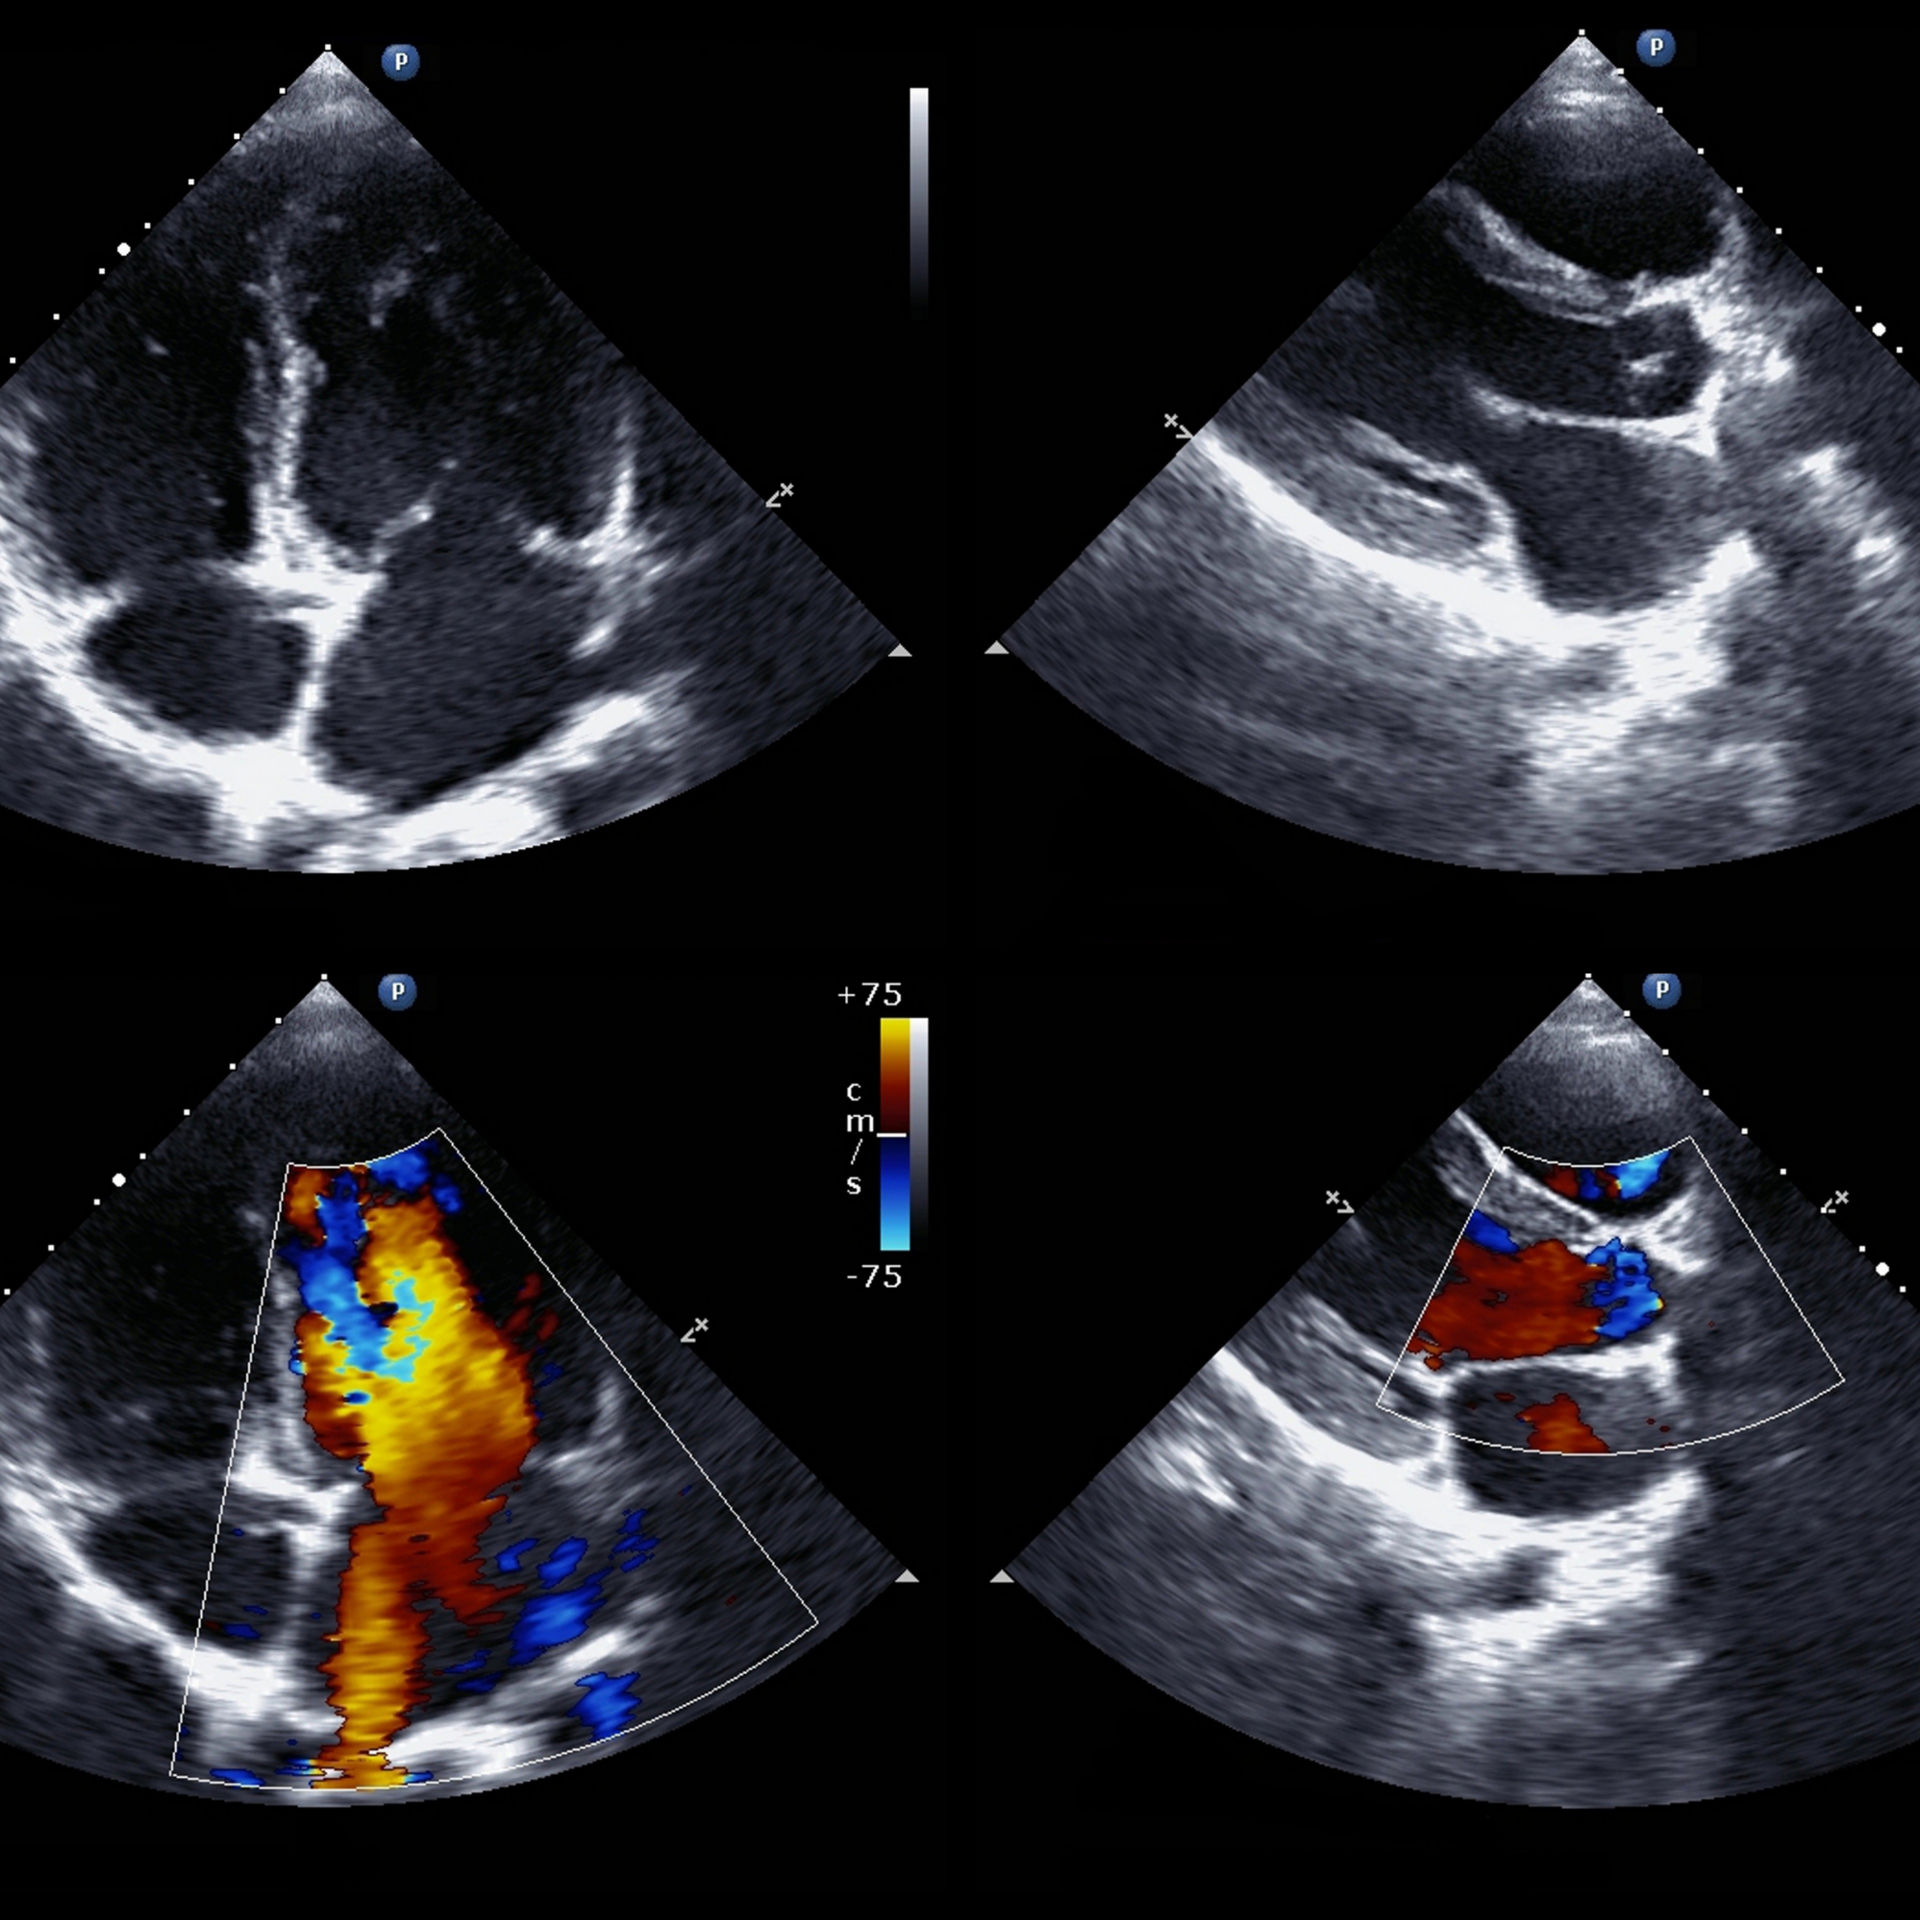

Ecocardiograma Doppler

El Ecocardiograma Doppler es un estudio de imagen no invasivo que utiliza tecnología de ultrasonido. Permite valorar en tiempo real el tamaño de las cavidades cardíacas, el movimiento del músculo cardíaco y el funcionamiento de las válvulas. Es fundamental en la evaluación de soplos, repercusiones cardiovasculares de pacientes hipertensos, síntomas como falta de aire y dolor torácico, así como para realizar un seguimiento de diversas enfermedades cardíacas.